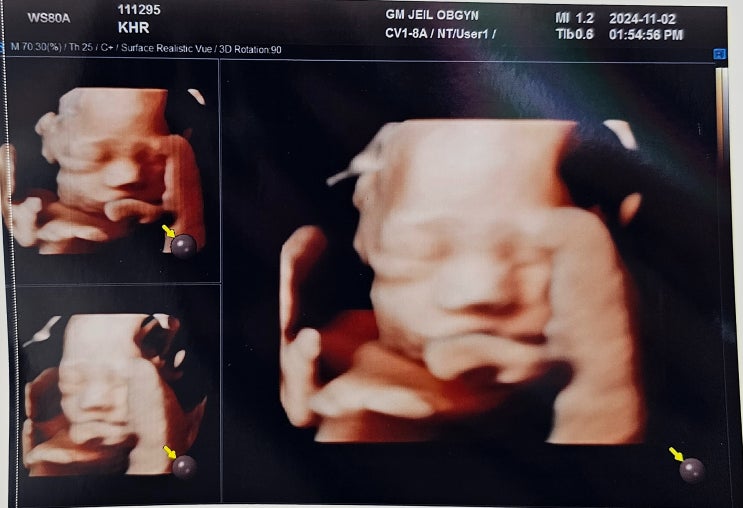

[28주 4일] 입체 초음파 보는 날! (Feat. 손목보호대, 압박스타킹 처방)

#임신일기 #28주4일 누구 닮았나~~~ 마지막에 얼굴 보여준 똑똑이! 28주 4일 - 심장소리 141 bpm / 몸무게 ...